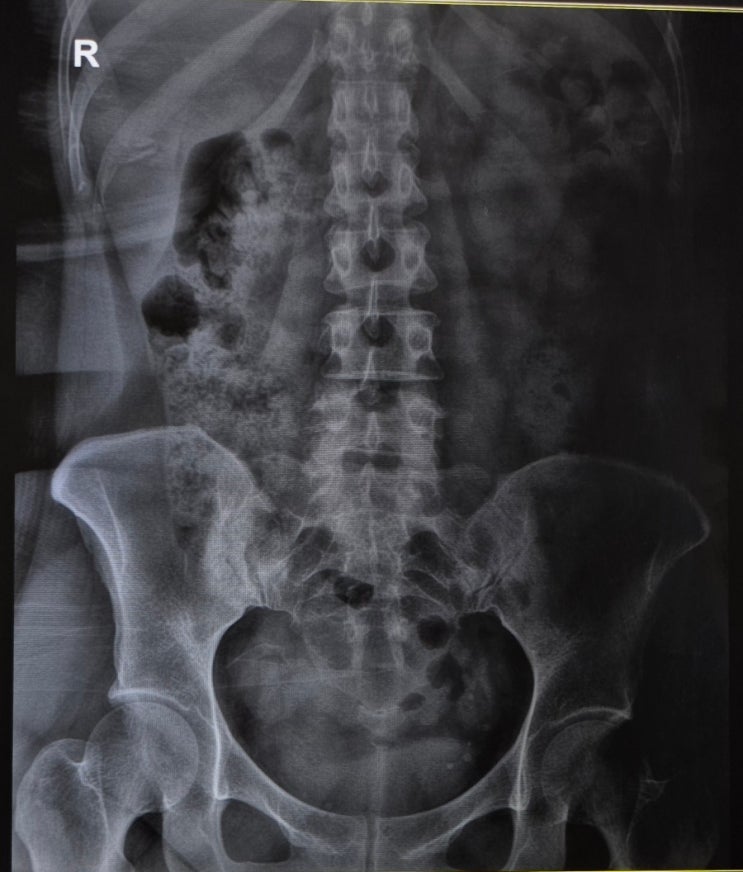

일자목, 일자허리, 목 디스크??

얼마 전 갑자기 아파 온 왼손, 물건을 들을 수도 힘을 줄 수도 없었다. 손가락 끝부터 팔꿈치까지 찬 냉기...